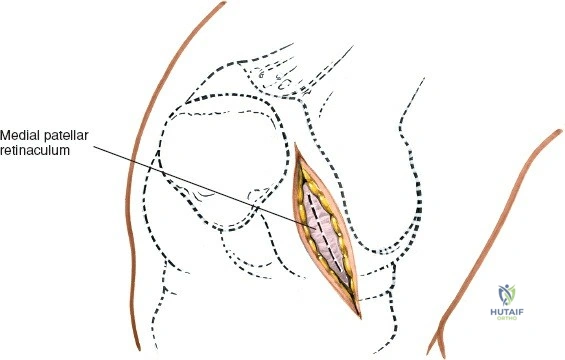

Landmarks and Incision:

- Landmarks: Palpate the medial joint line, medial epicondyle of the femur, and medial tibial plateau. The saphenous vein and nerve courses superficial and posterior to the medial femoral condyle, requiring careful attention.

- Incision Options (as per seed content):

- Transverse Skin Incision: "over the joint line; although this limits the view of the knee, it provides better access to the meniscus itself." This may be suitable for isolated, easily accessible mid-body tears.

- Longitudinal or Oblique Incisions: "offer a better view of such other intra-articular structures as the cruciate ligaments." These incisions provide broader exposure and are generally preferred for better visualization of the entire meniscus and other intra-articular structures. A paramedial, slightly curved longitudinal incision, approximately 5-7 cm in length, centered over the joint line, is a common choice. It extends from just above the joint line distally to just below.

- The choice of incision depends on surgeon preference and the specific pathology being addressed.

Dissection:

- Skin and Subcutaneous Tissue: Incise the skin and subcutaneous tissue. Meticulous hemostasis is maintained.

- Saphenous Nerve and Vein: Careful dissection is paramount to identify and protect the infrapatellar branch of the saphenous nerve and the greater saphenous vein, which lie within the subcutaneous fat layer. Retract them carefully.

- Deep Fascia: Incise the deep fascia.

- Joint Capsule: The approach typically involves either a medial parapatellar arthrotomy, splitting the fibers of the vastus medialis obliquus (VMO) longitudinally, or a direct incision of the medial capsule over the joint line, medial to the patellar tendon. For direct access to the medial meniscus, a paramedial capsular incision along the medial border of the patella and extending distally can be made.